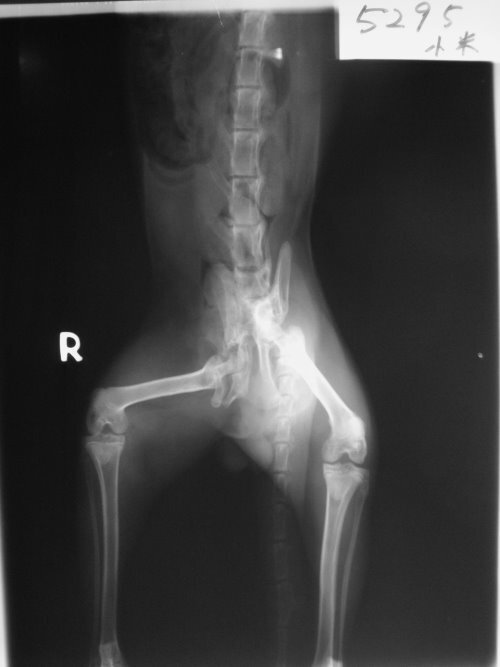

主題: 跛腳的貓咪 申請者姓名: 黃雅卉 花色: 申請日期: 2013-05-10 23:14:47 申請者部落格: 申請者臉書網址: 所在縣市/合作醫院: 高雄市/樂生動物醫院 治療費用: 24900元 需求人數: 26人 已結案 (2013-06-27 14:36:01) 報名人員: 胖姨 x26(已付款)、 候補人員: 動物病情說明: 在三民區灣愛里發現一隻貓咪走路跛腳,似行動有問題的貓咪,立即送醫經醫生診療,發現貓咪體內有許多排泄物,無法自行排出,X光檢查發現骨盆腔及腳骨折,骨盆變形壓迫導致排便困難,第一次緊急手術將腸切開把糞便取出,先解決積便可能會導致的巨結腸,術後貓咪狀況良好,先帶回中途照顧,每天餵食軟便劑和專用飼料,一個月後進行骨盆復位手術,因本人是學生無法支出這筆醫療費用懇求協會求助,請大家幫幫忙貓咪的兩次手術費用。謝謝!